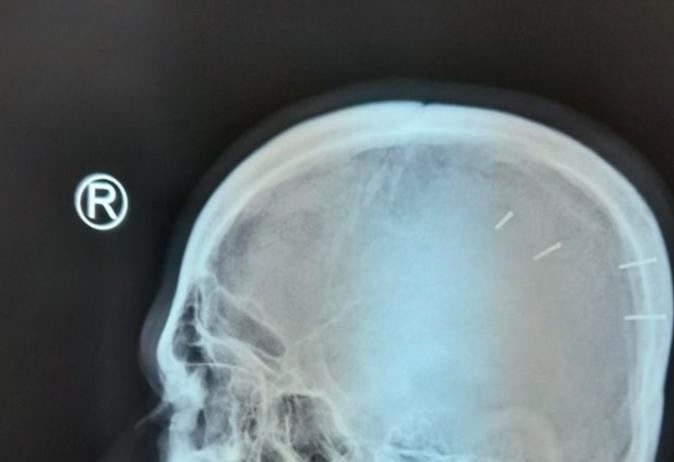

Hình ảnh X-quang cho thấy 4 cây đinh trong đầu bệnh nhân. Ảnh bệnh viện cung cấp

Sau khi chụp X-quang vùng đầu và qua lời kể của anh H., các bác sĩ xác định trong hộp sọ bệnh nhân này có dị vật là 4 cây đinh sắt dài 1,5 cm, đường kính khoảng 2 mm, nằm ở vùng thái dương bên trái.

Tiến hành phẫu thuật, các bác sĩ đã gắp ra được 4 cây đinh, bệnh nhân có dấu hiệu xuất huyết não nhẹ.

Theo nhận định của bác sĩ, do 4 cây đinh này ngắn, độ xuyên không cao, vừa hết phần xương sọ, chạm nhẹ đến màng não, không gây ra tình trạng xuất huyết não nặng nên bệnh nhân không ảnh hưởng đến tính mạng.